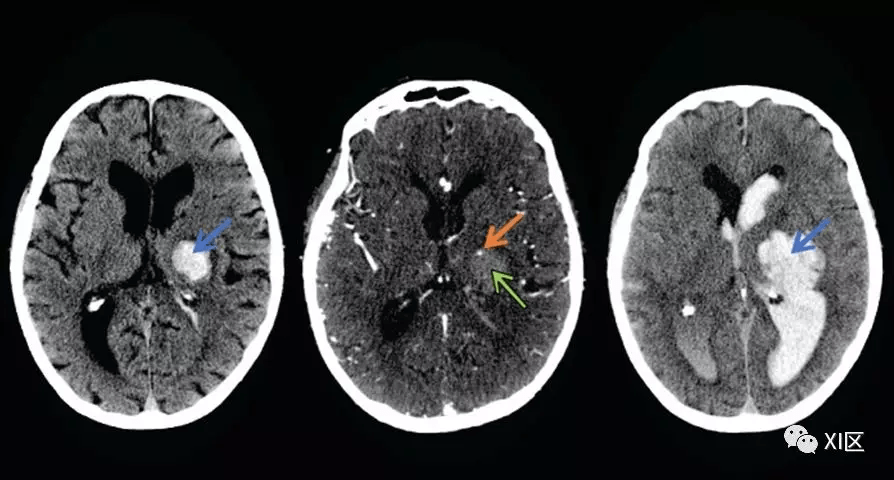

如何鉴别颅内出血?这些小技巧请收下!|识图断案

脑实质内出血丨演变,分布,ct表现